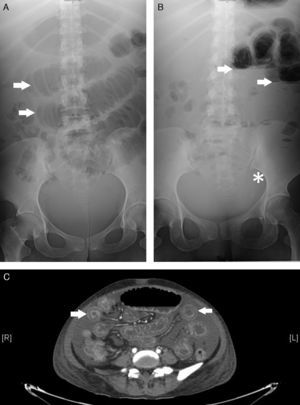

Se realizaron radiografías simples de abdomen donde se evidenciaba asas de intestino delgado dilatadas con imagen en pila de monedas (panel A) así como niveles hidroaéreos y ausencia de gas distal (panel B). La tomografía computarizada de abdomen confirmó la afectación del intestino delgado de manera difusa, con múltiples imágenes en «tiro al blanco» (panel C), que refleja engrosamiento de la pared del intestino delgado, y una captación aumentada de contraste, sin evidencia de perforación u obstrucción intestinal, lo que confirmó la sospecha de vasculitis mesentérica lúpica (VML).

Panel A muestra asas de intestino delgado dilatadas con el signo de “pila de monedas” (flechas). Panel B se observa las asas intestinales con niveles hidro-aéreos (flechas) al igual que la ausencia de gas distal (asterisco). Panel C se observan múltiples imágenes en “tiro al blanco” a lo largo de todo el intestino delgado.